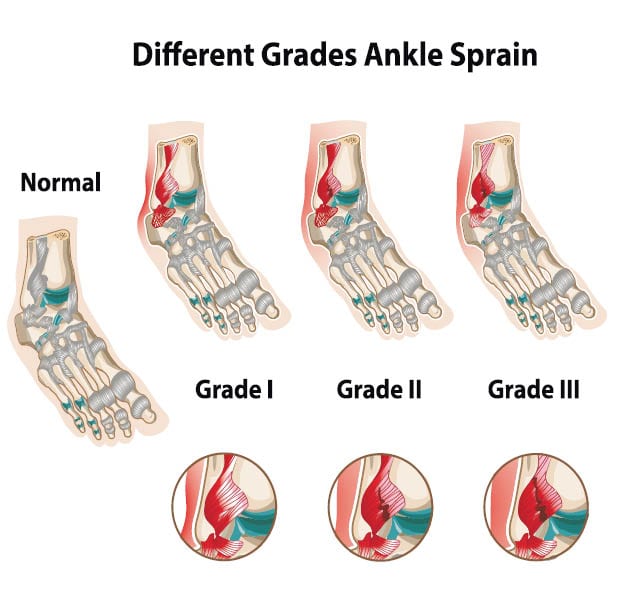

Grade 1 Sprains

Ankle sprains are classified by the severity of the ligament damage. With a grade 1 sprain, the ligaments are stretched but not torn. You may have mild pain and swelling but should not experience any loss of mobility or instability. You should not need to see a doctor unless you desire medical advice. With a minor sprain, you can begin physical therapy immediately and should be back in action in less than a week.

Grade 2 Sprains

A grade 2 sprain entails some tearing of the ligaments, but not a complete separation. You may experience swelling and pain that ranges from moderate to severe, as well as some joint instability. With this type of injury, you should start by keeping the ankle completely immobilized for several days. Sprained ankle recovery of this type usually takes four to six weeks. You probably don’t need to see a doctor unless the condition doesn’t improve.

Grade 3 Sprains

A grade 3 sprain occurs when the ligament is totally ruptured (or torn apart). Pain, swelling, and joint instability can be so severe that it is not possible to put any weight on the ankle. A doctor visit is often needed for this ankle sprain injury. An immobilization device like a hard cast is necessary for at least 10 days. Needless to say, this type of injury will take the longest to heal- three months or more. In some cases, a severe sprain will require surgery to repair the ligament.